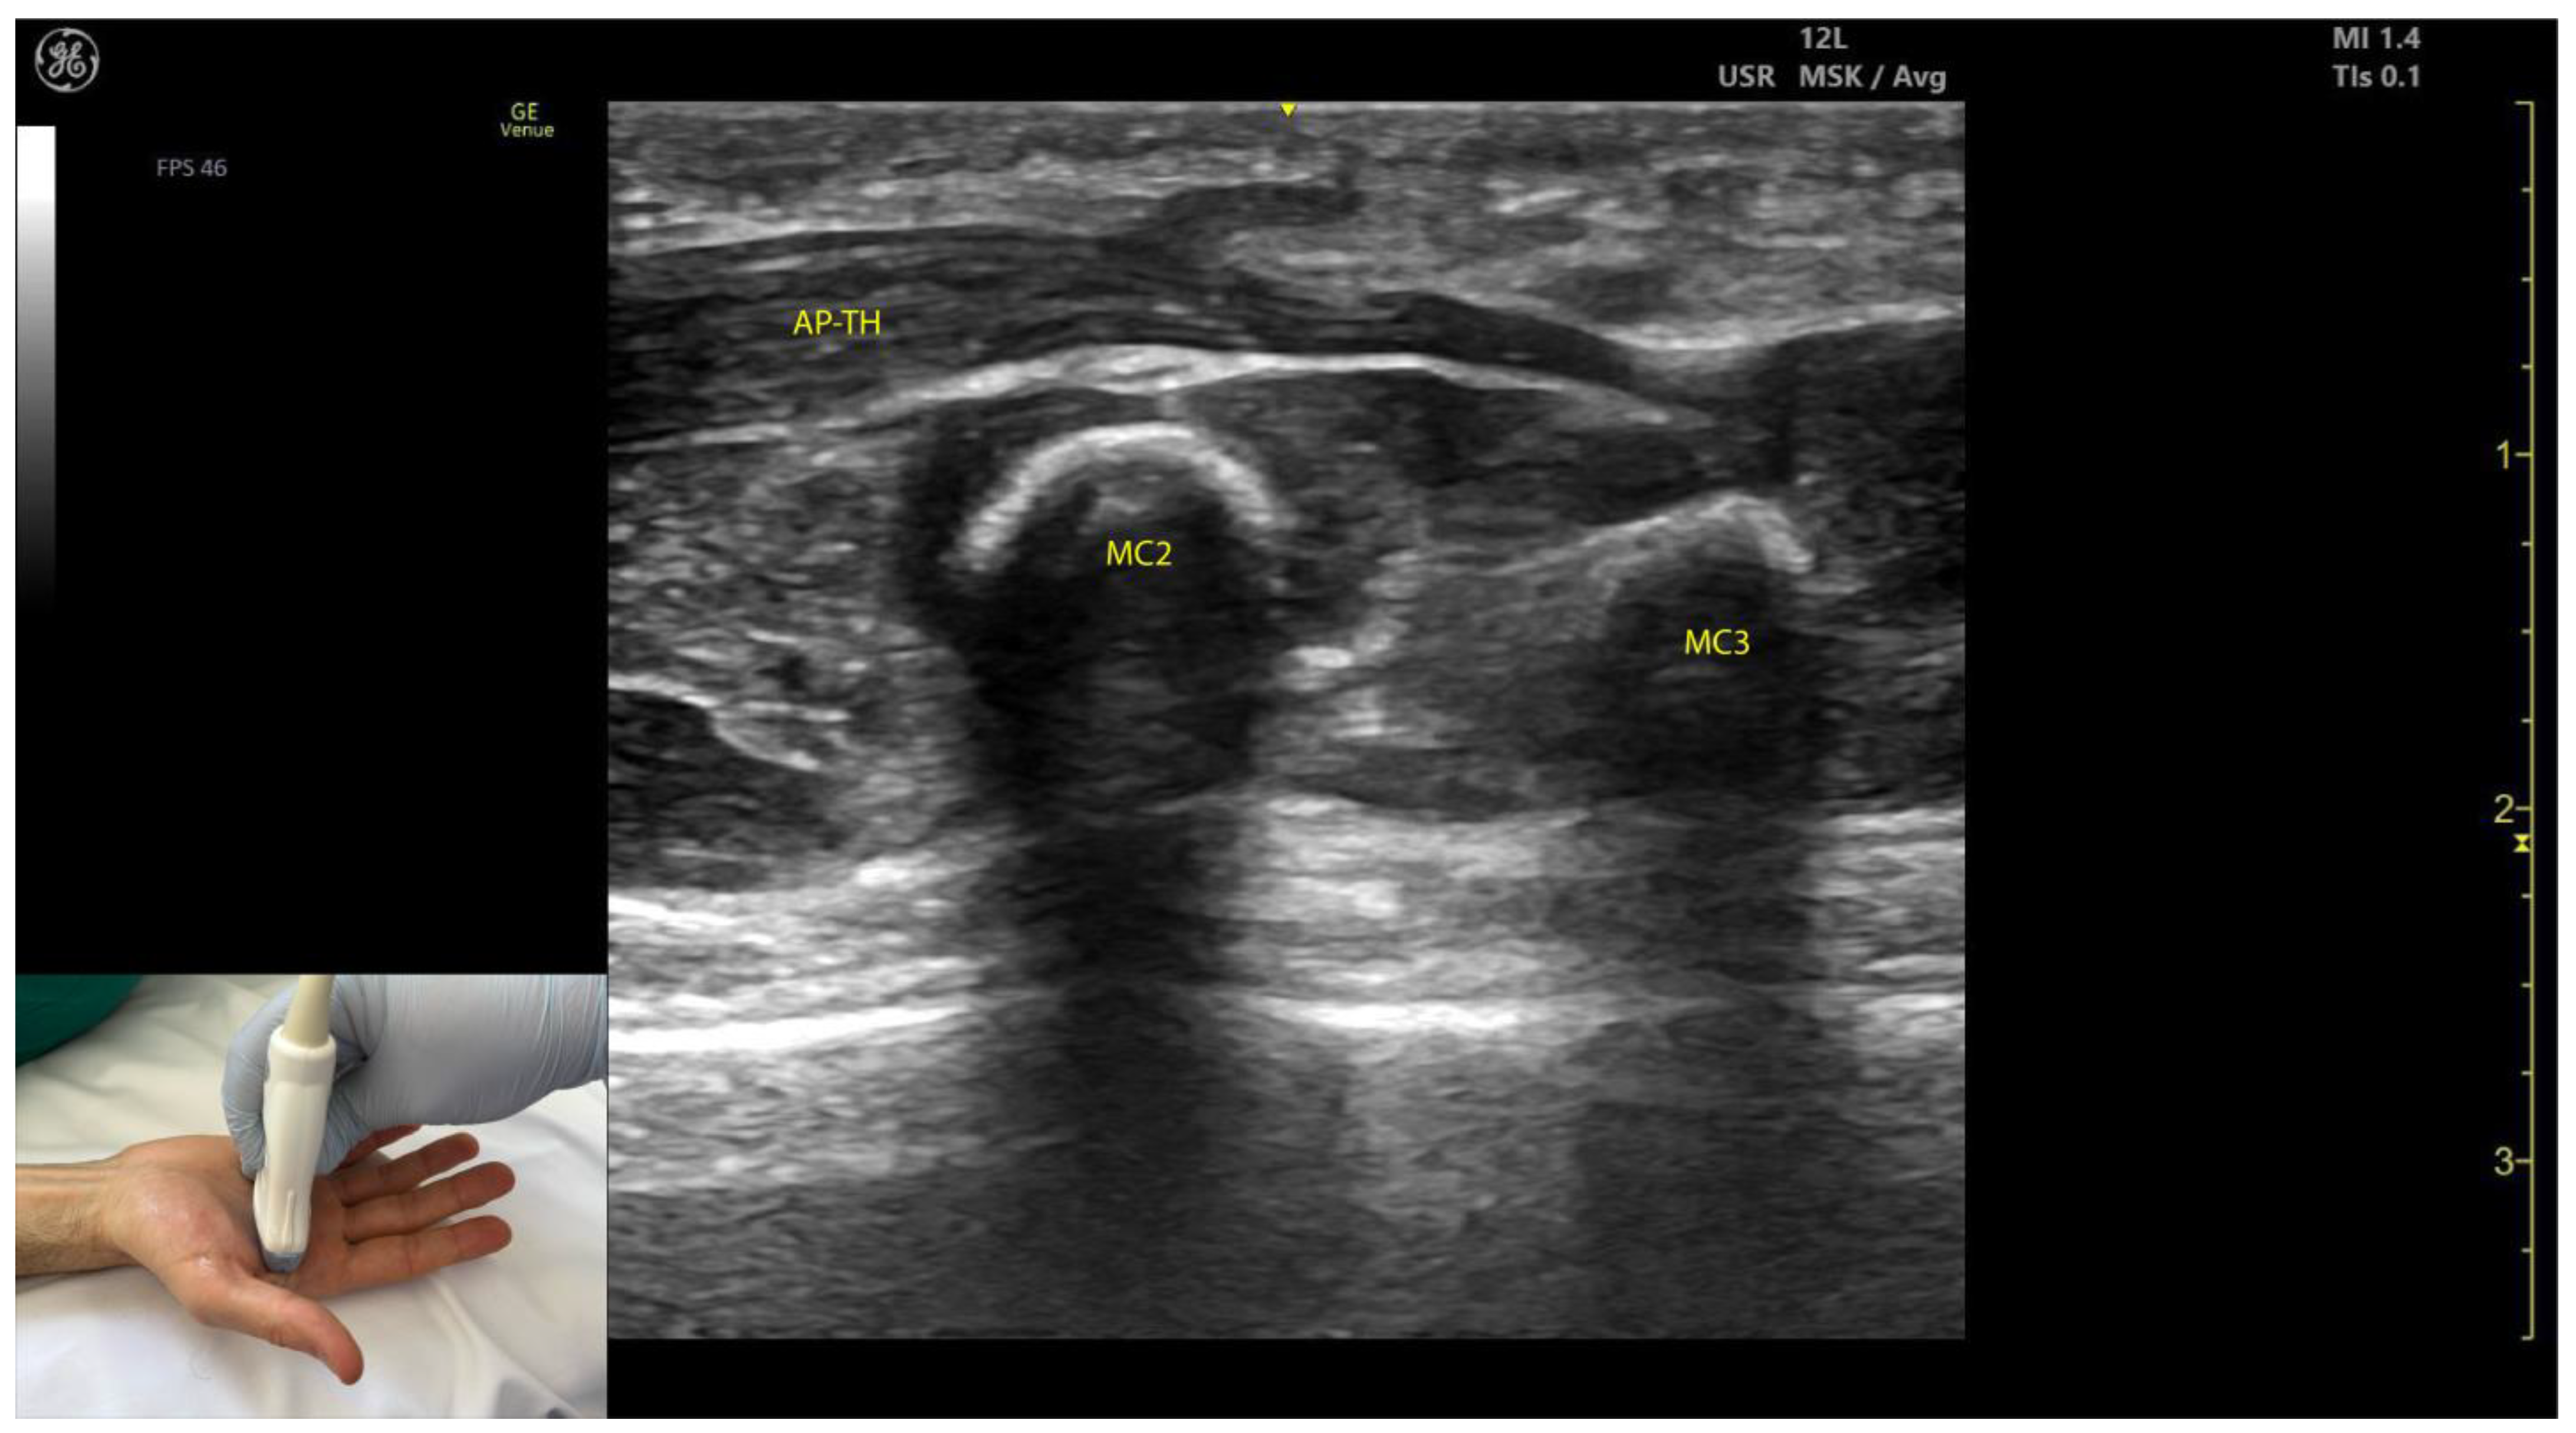

2.11.3. Key Ultrasound Landmarks (Figure 10 and Figure 11)

- Muscle size: The AP is larger than the muscles of the thenar eminence [58].

- Unique anatomical compartment: The AP is the only muscle in the adductor compartment of the hand [59].

- Two heads: The AP consists of a transverse head and an oblique head: (i) The transverse head is identified with the transducer placed transversely on the palmar aspect at the midpoint of the second and third metacarpals. Scanning proximally (approximately 1 cm) reveals the muscle’s maximal thickness; (ii) the oblique head is visualized by angling the transducer approximately 45 degrees laterally toward the thumb. This head is located lateral to the FPL tendon and the FPB, with the first dorsal interosseous muscle in its depth [59,60];

- External fascia: The AP muscle is characterized by a pronounced fascia that clearly separates it from adjacent muscle masses, facilitating precise localization during BoNT-A injections.

- Dynamic evaluation: Contraction of the AP is observed during thumb adduction at the CMC and MCP joints or during pinch movements, such as bringing the thumb tip into contact with the index finger tip.

2.11.4. Clinical Implications and Injection Strategy

- The AP is commonly injected with BoNT-A due to its critical role in thumb adduction, a movement it performs alongside the FPB and OP [61]. According to a 2023 study by Yi et al., the highest concentration of motor endplates is located on 1/5–3/5 of the muscle from the midline of the third metacarpal bone to the base of the first proximal phalanx [61].

- In our clinical practice, BoNT-A is administered into the point of maximum muscle thickness, as determined by ultrasound. The injection is typically performed approximately 1 cm proximal to the midpoint of the second and third metacarpals, with the transducer angled 45 degrees toward the thumb to target both the transverse and oblique heads.